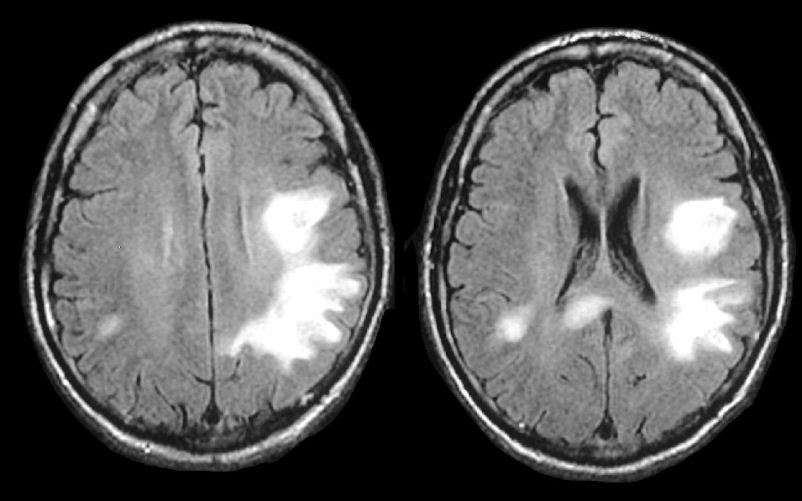

CADASIL/CARASIL

cerebral autosomal dominant/recessive arteriopathy with subcortical infarcts and leukoencephalopathy

NOTCH3 mutations

causes progressive cognitive decline, recurrent ischemic strokes (often lacunar), migraines

MRI features symmetric WM hyperintensities, including in anterior temporal poles